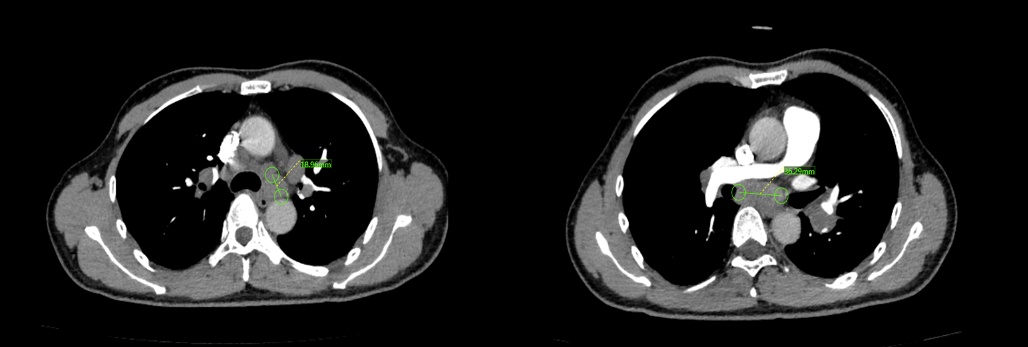

接诊的瑞金医院太仓分院呼吸与危重症医学科执行主任丁永杰仔细问诊、反复研读 CT 影像后,初步判断良性病变“结节病”可能性大,但必须拿到病理活检才能确诊及鉴别诊断。可一个难题横在眼前:患者肿大的淋巴结深藏在气道外的纵隔区域,这里解剖结构如同 “迷宫”,紧邻心脏、主动脉、肺动脉等关键器官,差之毫厘就可能危及安全,常规支气管镜无法到达,必须通过全麻下超声支气管镜引导经支气管针吸活检术(EBUS-TBNA)才能实现安全、精准穿刺取样。这项技术需要医生在超声实时监控下,用细针穿透气道壁,精准刺入淋巴结,全程避开大血管,对医生的技术、经验、判断力要求极高。EBUS-TBNA可有效探查常规支气管镜无法触及的纵隔、肺门等“盲区”,是纵隔淋巴结肿大病因诊断、肺癌术前分期的核心技术。

CT显示纵隔及肺门多组淋巴结异常增大